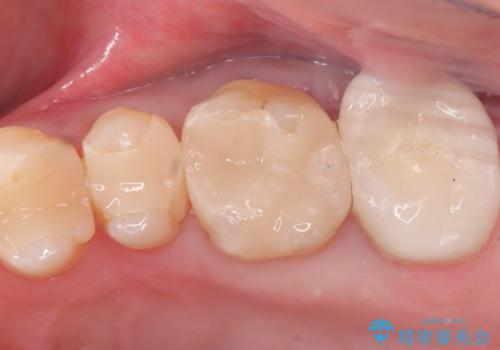

メタルインレーを丁寧に除去し、歯の状態を確認。その後、精密な形成を行い、適合性の高いセラミッククラウンを装着しました。セラミッククラウンは天然歯に近い見た目で、美しさだけでなく強度や機能性にも優れているため、患者様にも「自然な仕上がりで違和感なく噛める」と大変ご満足いただきました。